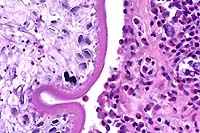

- Case 8-3. Kidney. One or more refractile protozoa

are found within many RBCs of congested interstitial capillaries.

There is fibrillar to amorphous proteinaceous material within

a collecting duct.

- Case 8-3 . Kidney. The glomerulus contains increased

numbers of mesangial cells which compress glomerular capillaries.

Adjacent tubules are filled with eosinophilic material forming